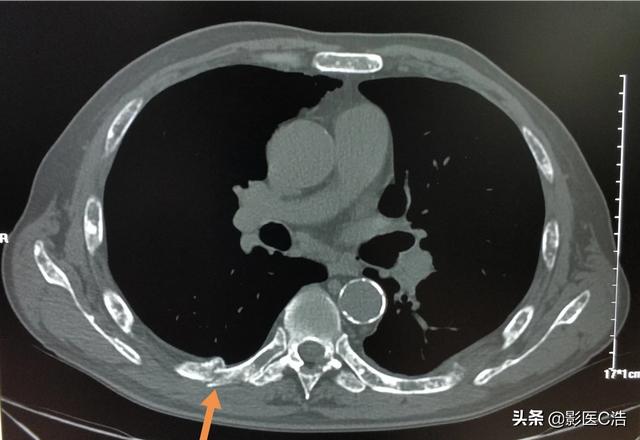

Il s'agissait d'une fracture pathologique causée par des forces externes mineures sur la base d'une métastase osseuse. Une ponction a été effectuée et la pathologie était une métastase osseuse d'un adénocarcinome pulmonaire peu différencié.

Ce nodule irrégulier dans le poumon gauche est le foyer principal, qui ne mesure que 2,6 cm. Un cancer du poumon avec des métastases osseuses comme celui-ci n'est plus opérable. On ne peut rien y faire, le cancer du poumon est trop fréquent et certains des premiers symptômes sont atypiques, voire asymptomatiques.Dans environ 30 % des cancers du poumon, les symptômes des métastases sont la première manifestation, et les métastases sont détectées en premier avant que d'autres cancers du poumon ne soient détectés.

Il s'agit de l'opération de fixation interne qu'il avait réalisée à l'époque pour une fracture de la clavicule, une fracture pathologique qui a beaucoup de mal à guérir seule sans intervention chirurgicale.